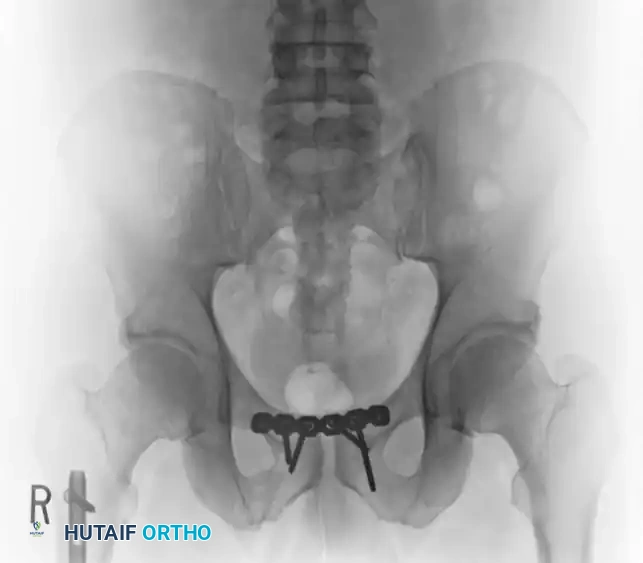

Case 3: Young-Burgess Anteroposterior Compression Type III (AP III)

An AP III injury is a completely unstable pelvic ring disruption. It involves complete disruption of the symphysis pubis (or anterior rami) and complete disruption of both the anterior and posterior sacroiliac ligamentous complexes. The hemipelvis is both rotationally and vertically unstable.

Preoperative Evaluation:

The preoperative AP, inlet, and outlet views demonstrate severe pubic diastasis, bilateral pubic rami fractures, and gross widening/displacement of the posterior SI joints.

Axial CT imaging confirms the complete dissociation of the sacroiliac articulation, highlighting the profound instability of the posterior tension band.

FIGURE 56-45: Young and Burgess anteroposterior type III (AP III) pelvic ring injury with pubic diastasis and bilateral pubic rami fractures. A-C, Preoperative anteroposterior, inlet, and outlet views, respectively. D, Preoperative CT scan.

Surgical Management:

AP III injuries require robust anterior and posterior fixation. Anteriorly, a symphyseal plate or external fixator is applied. Posteriorly, percutaneous iliosacral screws (placed into the S1 and/or S2 vertebral bodies) or posterior tension band plating is required to counteract vertical shear forces and allow for early mobilization.